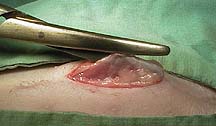

The uterus needs to be exteriorized from the abdomen for the spay to proceed. In this view one horn of the uterus is exposed. The arrow points to the location of the ovary, buried in fat.